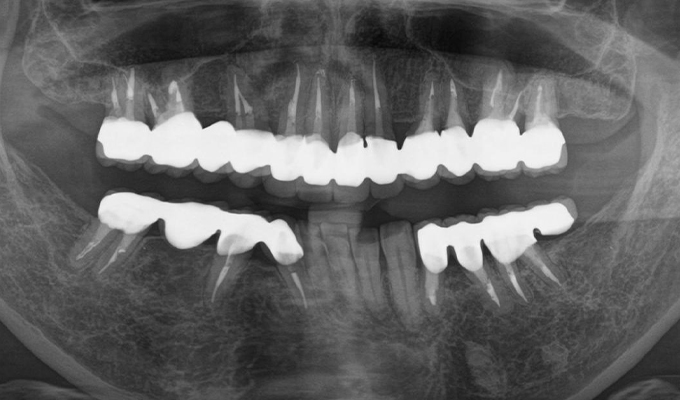

- 全体的に歯周病があり(平均ポケット数値6~7mm)、そのせいで動揺している歯も多数あったためまず歯周病の治療を行いました。

平均ポケット数値が2~3㎜になったところで補綴治療を開始しました。歯のない部分はインプラントを入れ、ブリッジはハイブリットセラミックスで入れました。

2014年に治療が終わった後もメンテナンスに定期的に通っていただきナイトガードも使用していただいてます。きれいな状態が維持されています。